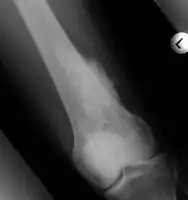

Medical imaging usually shows a well-defined wide-based bony growth on the surface of bone.[5] It can be pedunculated and irregular, giving it a "bizarre" appearance, and is not connected to underlying bone.[2]

MRI mid-upper arm

MRI mid-arm axial view